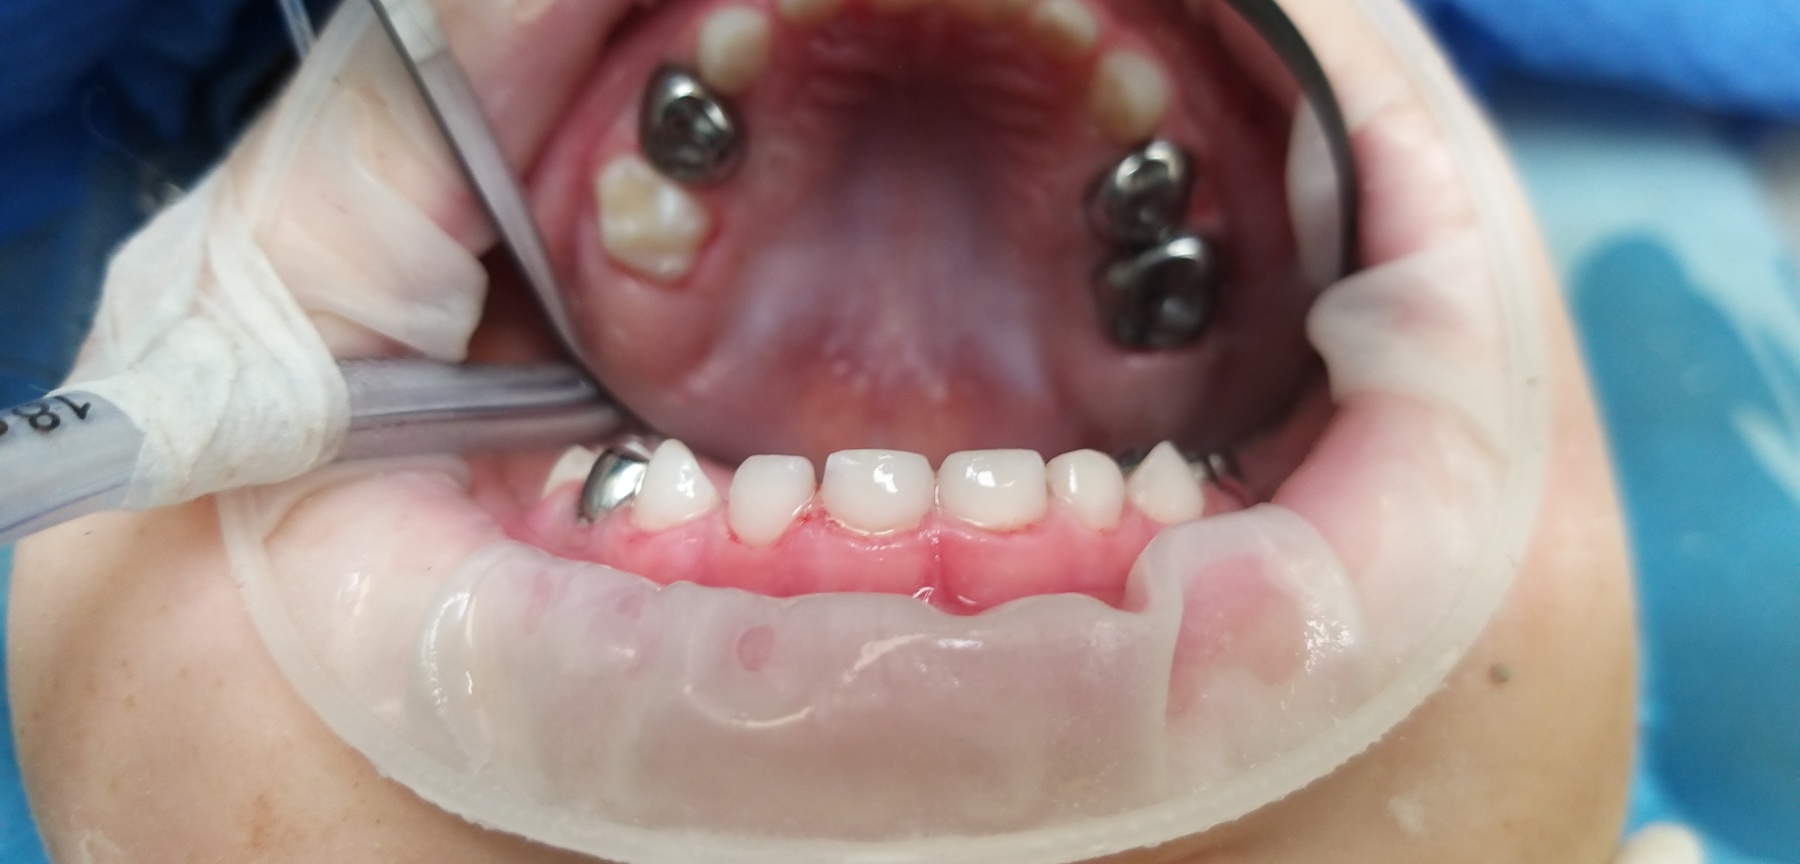

Стартувавши у 2009 році як одна з перших приватних клінік у Борисполі, «Здорова усмішка» і до сьогодні впевнено утримує позиції лідера на ринку стоматологічних послуг. Все це завдяки багаторічному досвіду, дотриманню чітких стандартів якості та постійному впровадженню інновацій. Свідченням цього є усмішки не лише киян, а й пацієнтів з багатьох країн світу.

Час не стоїть на місці, і ми впевнено крокуємо разом з ним. Щороку з’являються дієві методики та нові підходи, сучасні матеріали, які ми активно застосовуємо в процесі лікування. Аби забезпечити найвищий рівень послуг, ми постійно вдосконалюємось та навчаємось, беручи активну участь в різних галузевих виставках, семінарах та конференціях.

Ми працюємо тільки з найкращими матеріалами: Нанокомпозити Filtek виробництва США.